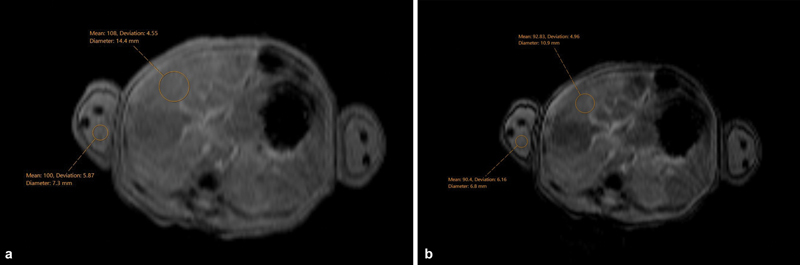

Background  Gestational alloimmune liver disease (GALD) is characterized by maternal IgG-directed fetal hepatocyte damage and can lead to severe liver failure and fetal or infant death. Moreover, GALD is associated with a near 90% risk of recurrence in subsequent pregnancies. Case  We present a case of a newborn patient delivered to a 32-year-old G2P1000 mother who received prolonged antenatal intravenous immunoglobulin (IVIG) treatment during the current pregnancy due to the neonatal death of the first child from GALD-related liver failure. Postnatal testing, including a liver magnetic resonance imaging (MRI) and buccal biopsy of this newborn, showed normal morphology of the liver without any abnormal iron deposition. Additional laboratory testing showed a lack of any liver injury. Conclusion  This case supports the use of antenatal IVIG immunotherapy to prevent the recurrence of GALD in subsequent pregnancies. Key Points GALD can lead to severe fetal liver injury.GALD is highly recurrent in subsequent pregnancies.Prophylactic IVIG may prevent GALD recurrence.

Abstract Image